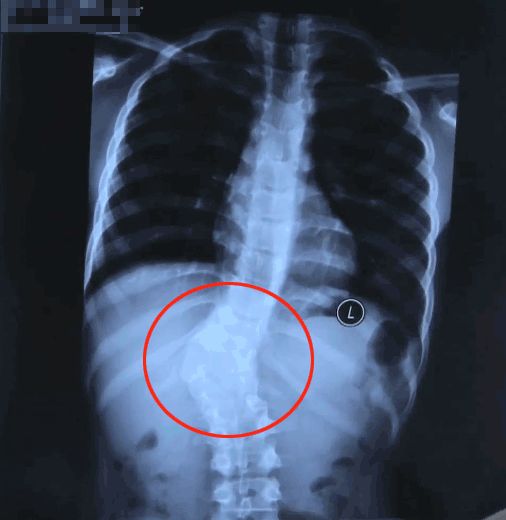

為了進一步查明塔吉脊柱側彎的真相,伊力為她做了站立位脊柱全長 X 線片檢查。

從 X 線片中可以看出,塔吉的脊柱有明顯的側彎。